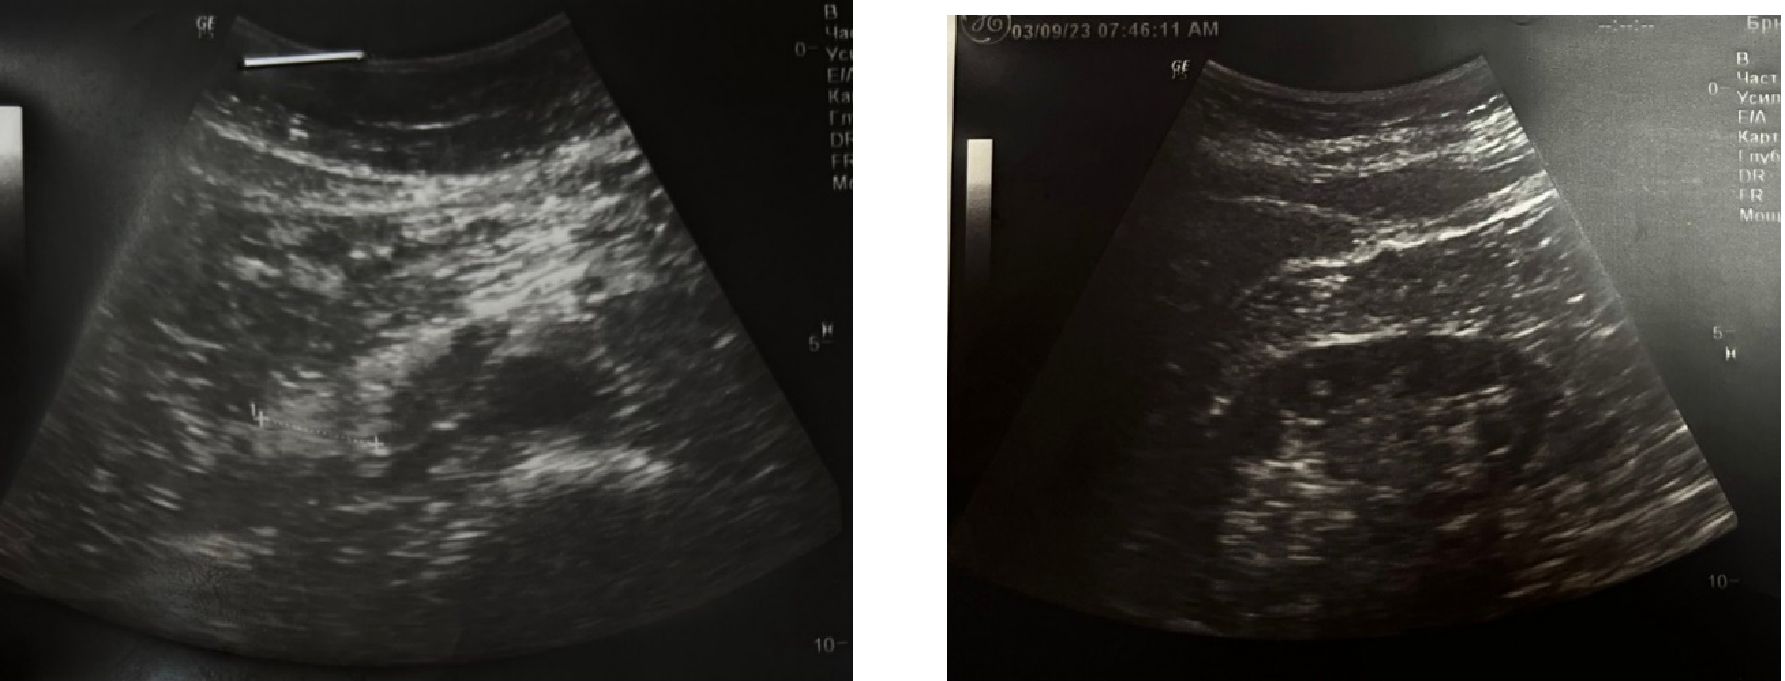

Рис. 1. Диффузные изменения паренхимы почек. Двухсторонний нефроптоз

Ультразвуковое исследование абдоминальное от 09.03.2023

Заключение: УЗ признаки: Диффузных изменений в печени, поджелудочной железе. Застоя в желчном пузыре. Уплотнение полостной системы и диффузных изменений в паренхиме почек. Нефроптоз. Метеоризм. Атеросклероза аорты.